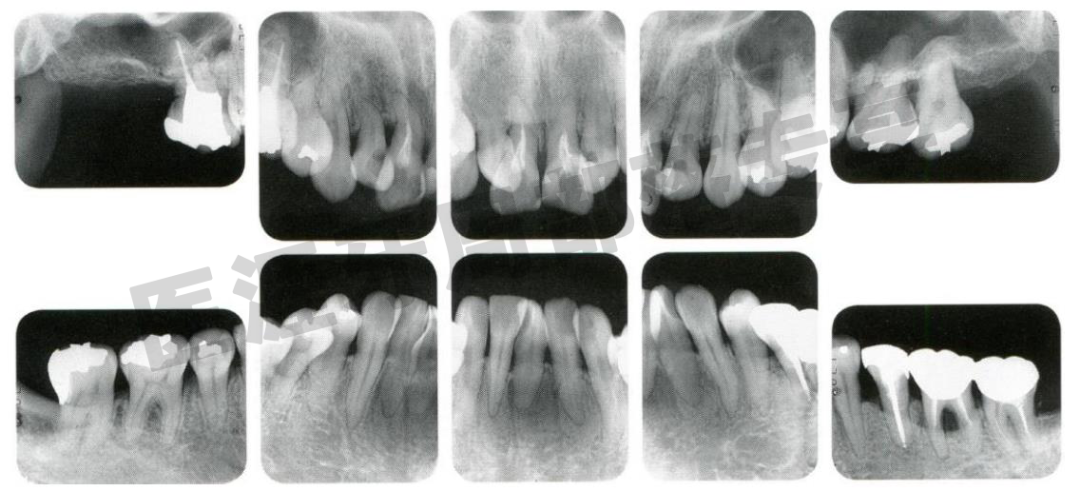

5.临床病例

初诊时33 岁的女性患者

怎么选洁牙器械5个要点带你学习器械洁牙_https://www.jmylbn.com_新闻资讯_第36张

初诊时口内照(1997 年11 月) 虽有菌斑附着,但刷牙情况并不特别差

怎么选洁牙器械5个要点带你学习器械洁牙_https://www.jmylbn.com_新闻资讯_第37张

初诊时X 光片(1997 年11 月)

全口可见骨吸收,还有歪斜的牙根,考虑较高牙周炎风险。